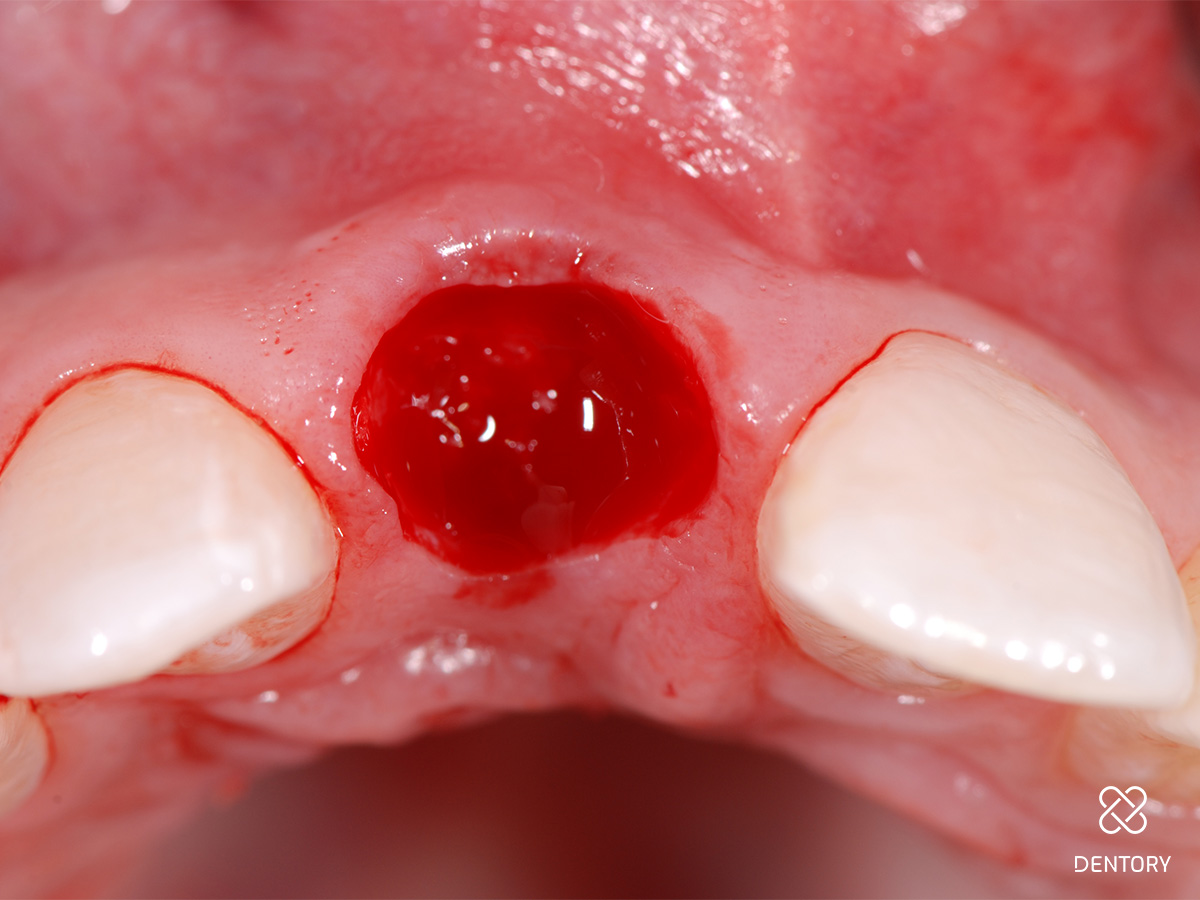

Abbildung 5

Sondieren der bukkalen Knochenstrukturen mittels Biotyp-Sonde; im Bereich der Resorption kam es zum lokalen Verlust der vestibulären Lamelle.